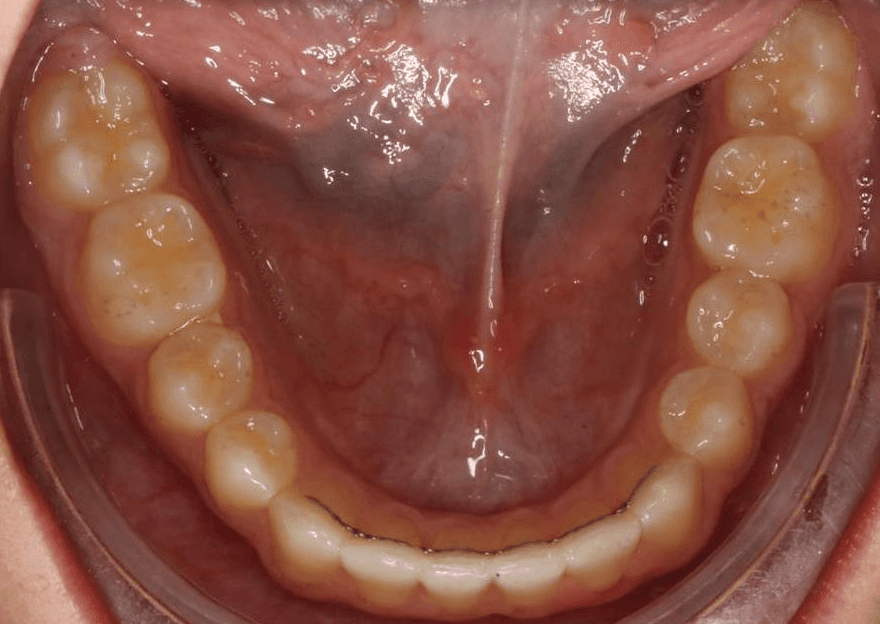

Female, 14 | Treatment time: 21 months

Diganosis: Lower anterior crowding, mild maxillary spacing, misalignment of anterior teeth, rotated premolars and molars

Final results

INTRAORAL